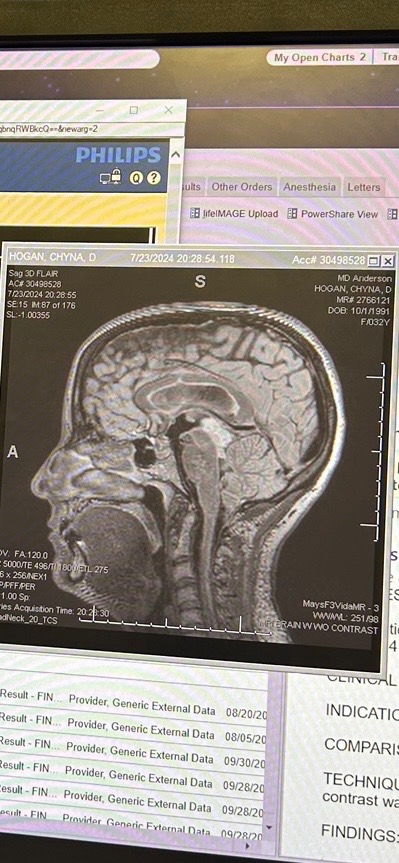

My beautiful daughter, Chyna, was diagnosed with an inoperable brain tumor about 2 years ago. Living with this uncertainty and being a full-time, working, single mother to my spectacular 4 year old granddaughter, Adah, has been a difficult path for my daughter. The tumor is growing slowly each year. And living with the symptoms daily and the stress of distinguishing a common headache or escalating symptoms of the tumor is a very daunting way of life for Chyna.